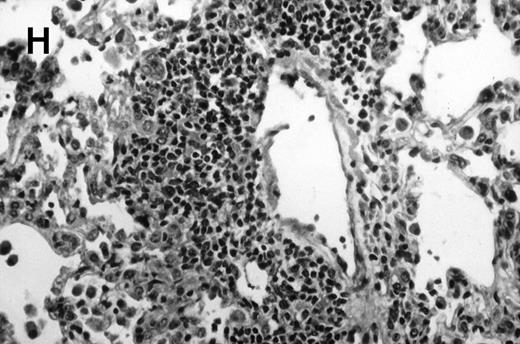

Allogeneic transplanted mice (B10.BR → CBA) with GVHD and, as controls, allogeneic transplanted mice without GVHD and syngeneic transplanted mice (B10.BR → B10.BR) were infected intranasally with HSV-1 at 12 weeks after transplantation. As an additional control, age-matched normal CBA mice were infected as well. Histological examination of lungs was performed in mock-infected mice and in mice at day 7 after infection. Allogeneic transplant recipients with GVHD showed increased pathology (Fig 1). Scores reflecting the periluminal histopathologic changes were significantly higher (P = .05; Student's t-test) in allogeneic transplant recipients with GVHD, when compared with control mice (Fig 2). The periluminal histopathologic scores were also higher in allogeneic transplant recipients with GVHD, when compared with normal CBA mice, at days 4, 10, and 14 after infection (data not shown). No significant differences were observed in the scores reflecting the parenchymal histopathologic changes (data not shown). Because the results in syngeneic transplanted mice were very similar to those in allogeneic transplanted mice without GVHD, the latter, which are the most appropriate control for procedural effects and for the effect of GVHD, and normal CBA mice, were used as controls in further experiments.

Allogeneic transplant recipients with GVHD showed increased pathology. Photomicrographs of lung sections stained with hematoxylin and eosin show evidence of increased pathology in infected allogeneic GVHD mice. (A) Normal CBA, mock-infected, original magnification × 25; (B) normal CBA, mock-infected, original magnification × 100; (C) normal CBA, infected, original magnification × 40; (D) normal CBA, infected, original magnification × 100; (E) allogeneic GVHD, mock-infected, original magnification × 10; (F) allogeneic GVHD, mock-infected, original magnification × 75; (G) allogeneic GVHD, infected, original magnification × 10; (H) allogeneic GVHD, infected, original magnification × 100.